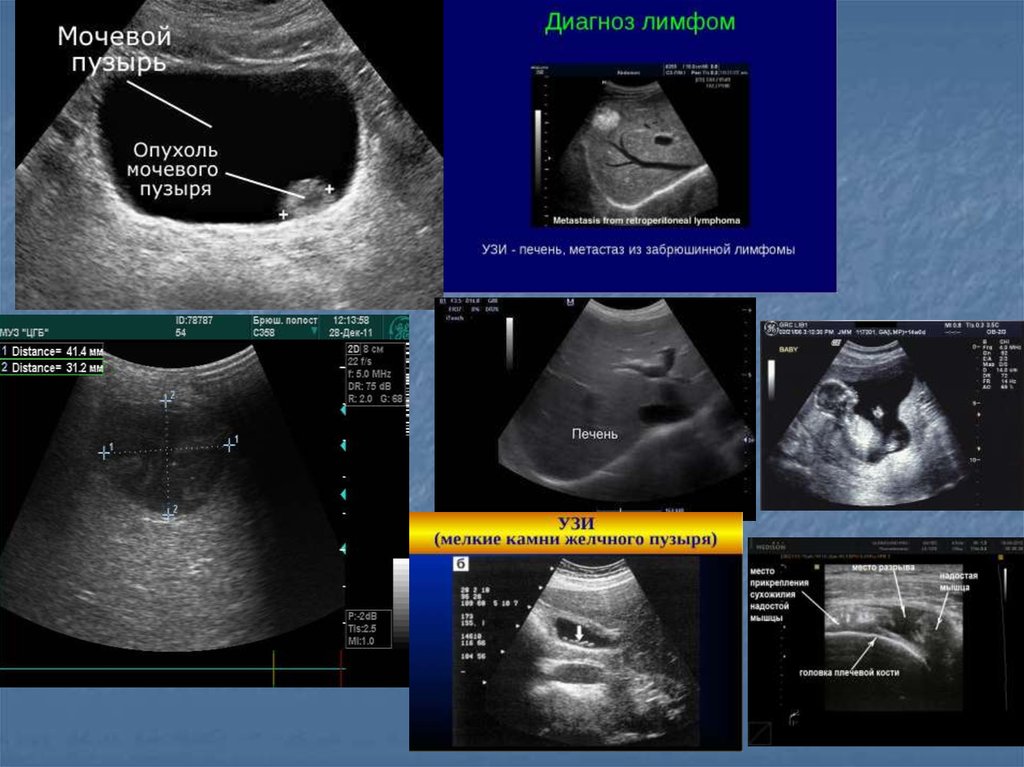

36. Показания

Воспалительные заболевания брюшной полости,

малого таза и шеи…

Наличие жидкости в брюшной и грудной полостях, в

суставах

Визуализация мягких тканей(мышцы, связки,

околосуставные пространства)

Желчекаменная, почечнокаменная болезни

Диагностика опухолей (молочная железа, яичники,

лимфоузлы)

Заболевания сосудов(варикозная болезнь,

эндортереит, оартиты, аневризмы, ангиопатия)

Врожденные и воспалительные заболевания

сердца(пороки клапанного аппарата, дефекты

стенок, нарушение функции миокарда, эндокардит,

перикардит)